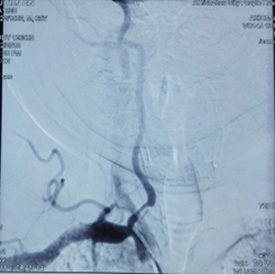

图为左侧椎动脉起始段狭窄手术前DSA 图为右侧椎动脉起始段狭窄手术前DSA